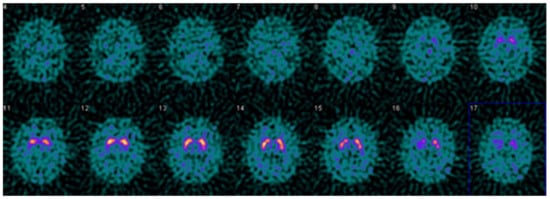

Figure 4.

Example DaTQUANT results in a non-PS patient demonstrating apparent loss of the normal “comma shape”, particularly on the right. However, none of the summary measures, SBR (1.23 to 1.33), z-score (−0.51 to −0.88), or percent deviations (−0.12 to −0.19) meet thresholds for abnormal. The caudate nuclei are noted to have relatively increased uptake (SBR 3.10–3.45, z-score 2.42–3.48) causing an apparent decrease in putaminal activity where there is none (“hot caudate” sign).